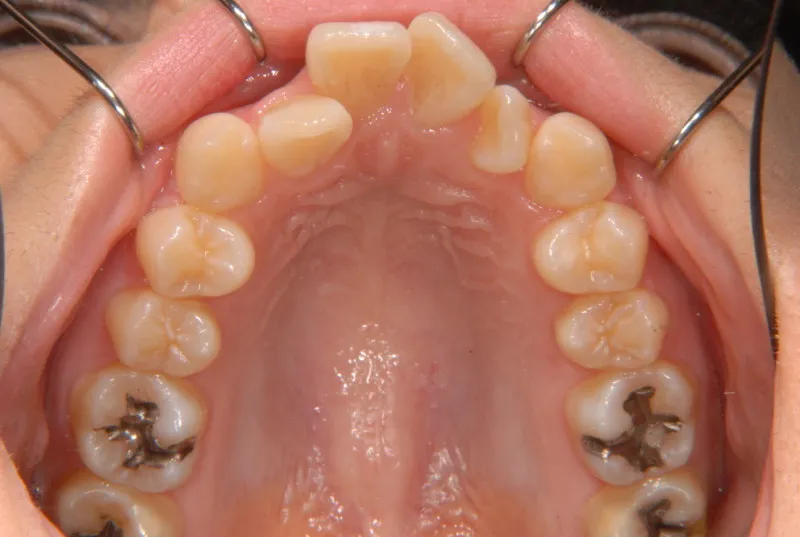

奥歯が内側と前方にかたむき上下の歯がガタガタに生えています。

90度ねじれた歯もあります。前歯も出っ歯になっています。

歯は抜かず、歯科矯正用アンカースクリューを用いて治療しました。

初診時